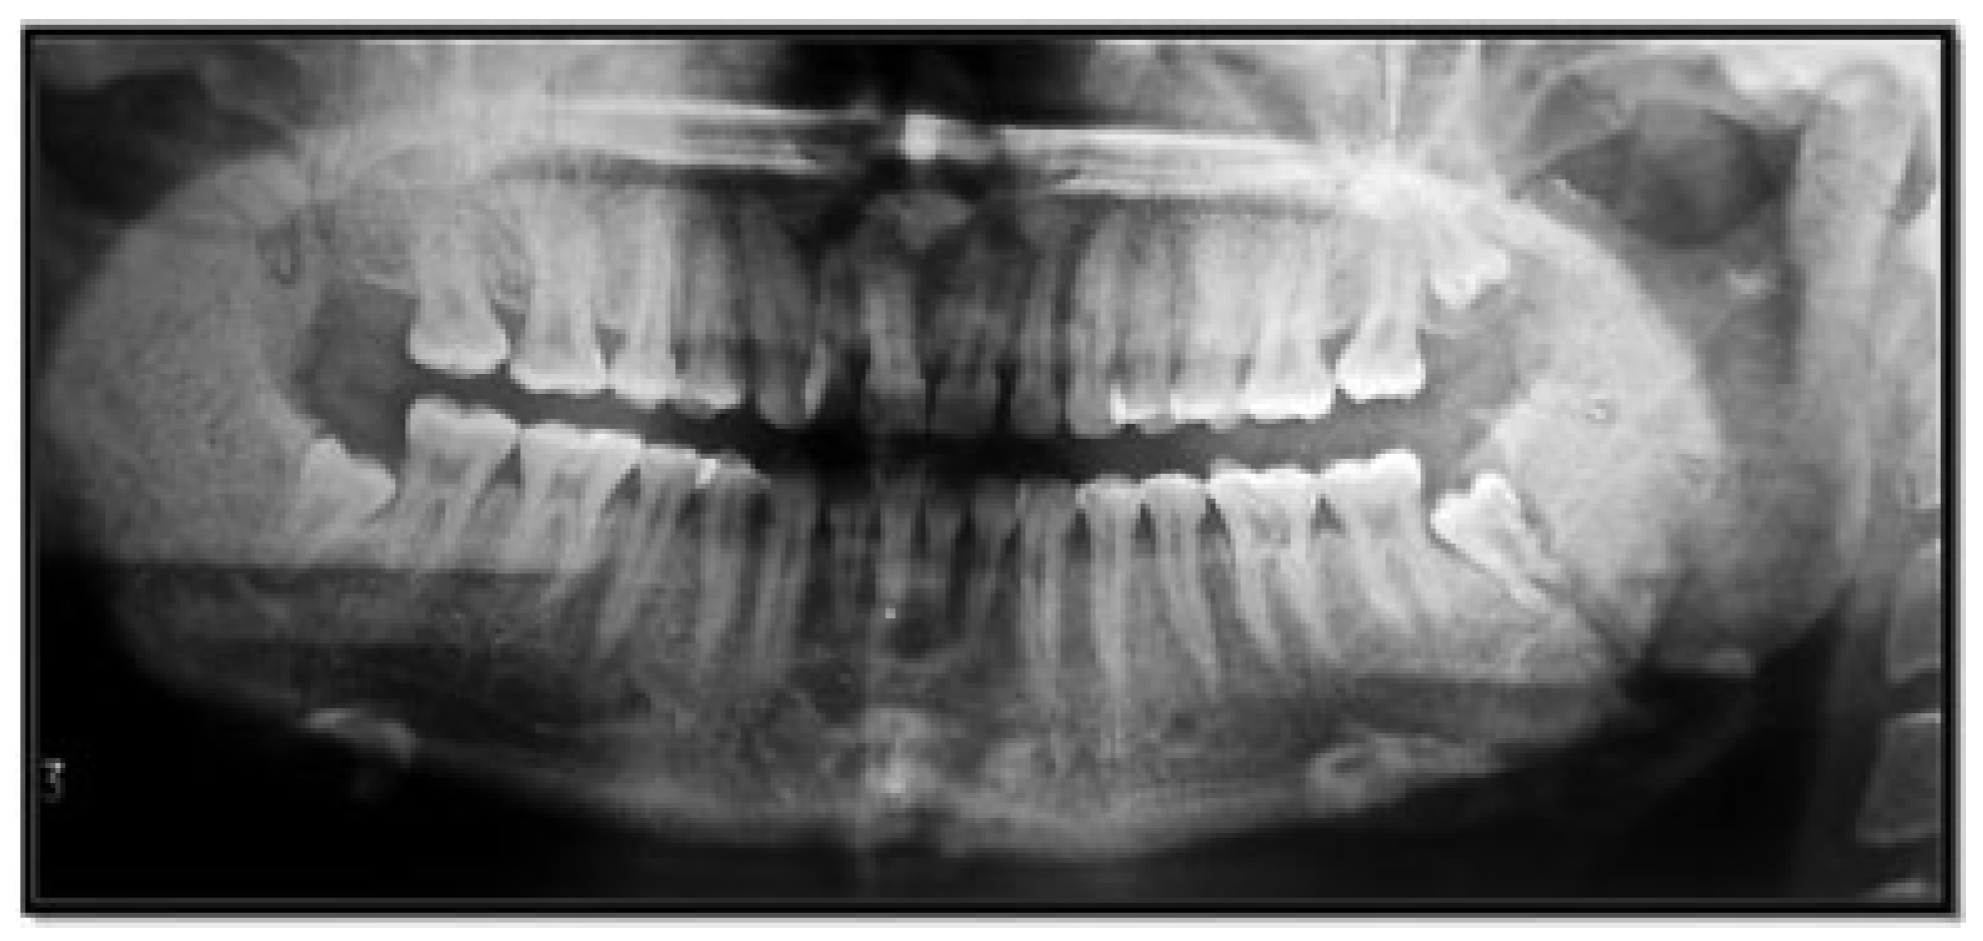

Of the condyle fractures, 76 patients (58.46%) had absence of mandibular third molars, whereas 54 patients (41.54%) had third molars. The absence of a mandibular third molar in condylar fractures was statistically and significantly higher than in patients where third molars were present (Figure 5, Figure 6, Figure 7 and Figure 8; Table 4).

Figure 5. Angle fracture with the presence of impacted mandibular third molar.